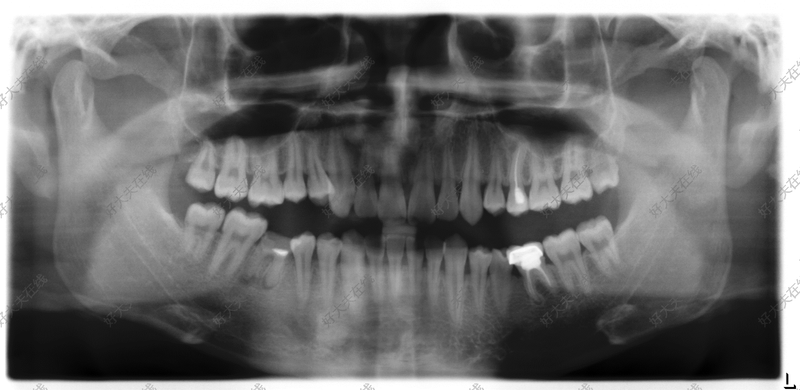

治療前 患者男,23歲,深覆合,伴下頜雙側(cè)第一磨牙嚴(yán)重齲壞,下頜兩側(cè)智齒均形態(tài)較好,牙根健康??紤]到患者的年齡及主訴。拔除兩顆第一磨牙后,采用下頜智齒前移替代。 治療中 采用固定矯正,近中移動磨牙關(guān)閉間隙。 治療后 治療后0天 患者矯正結(jié)束時實現(xiàn)中性咬合關(guān)系,覆合覆蓋正常。下頜雙側(cè)智齒完全替代原本已經(jīng)齲壞的磨牙。治療效果較好。